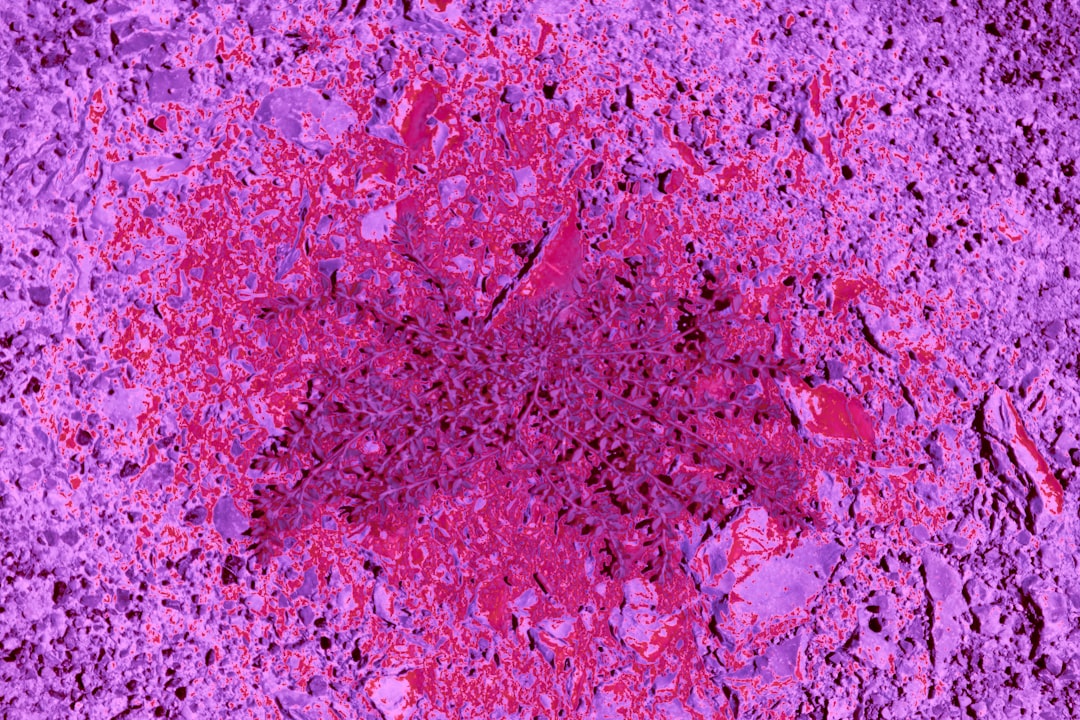

난소종양은 여성에게 생길 수 있는 여러 질환 중 하나로, 증상이 뚜렷하지 않아 초기 발견이 어려운 경우가 많습니다. 난소종양 증상 중 가장 일반적인 것은 복부 팽만감입니다. 이는 영향을 받는 난소가 비대해지면서 주변 장기에 압박을 가하거나 체액이 축적될 수 있기 때문입니다. 또한, 반복적인 하복부 통증이나 생리주기의 변화도 나타날 수 있습니다. 이럴 때는 반드시 전문의를 찾아 상담하는 것이 중요합니다.

난소종양의 치료 방법에는 여러 가지가 존재합니다. 우선, 난소종양 수술은 종양의 크기와 유형에 따라 다르게 진행됩니다. 보통 양성 종양이라면 수술을 통해 제거하는 것이 일반적이지만, 악성 종양일 경우에는 추가적인 치료가 필요할 수 있습니다. 이를 위해 환자의 상태를 면밀히 평가하는 것이 중요합니다.

난소종양에 대한 진단과 관련하여 알아두어야 할 사항들이 있습니다. 난소 물혹 양성종양 차이를 이해하기는 매우 중요합니다. 양성 물혹은 대개 증상이 없지만, 시간이 지나면서 크기가 커질 수 있으므로 관찰이 필요합니다. 반면에 악성 종양은 진단 후 즉각적인 대응이 필요할 수 있습니다.

특히 난소 경계성종양의 경우는 말 그대로 악성과 양성 사이의 상태로, 진료 시 각별한 주의가 필요합니다. 초기에는 일반적으로 치료가 가능하지만, 이를 간과할 경우 회복이 어려워질 수 있습니다. 따라서 정기적인 건강 검진이 중요한 이유입니다.